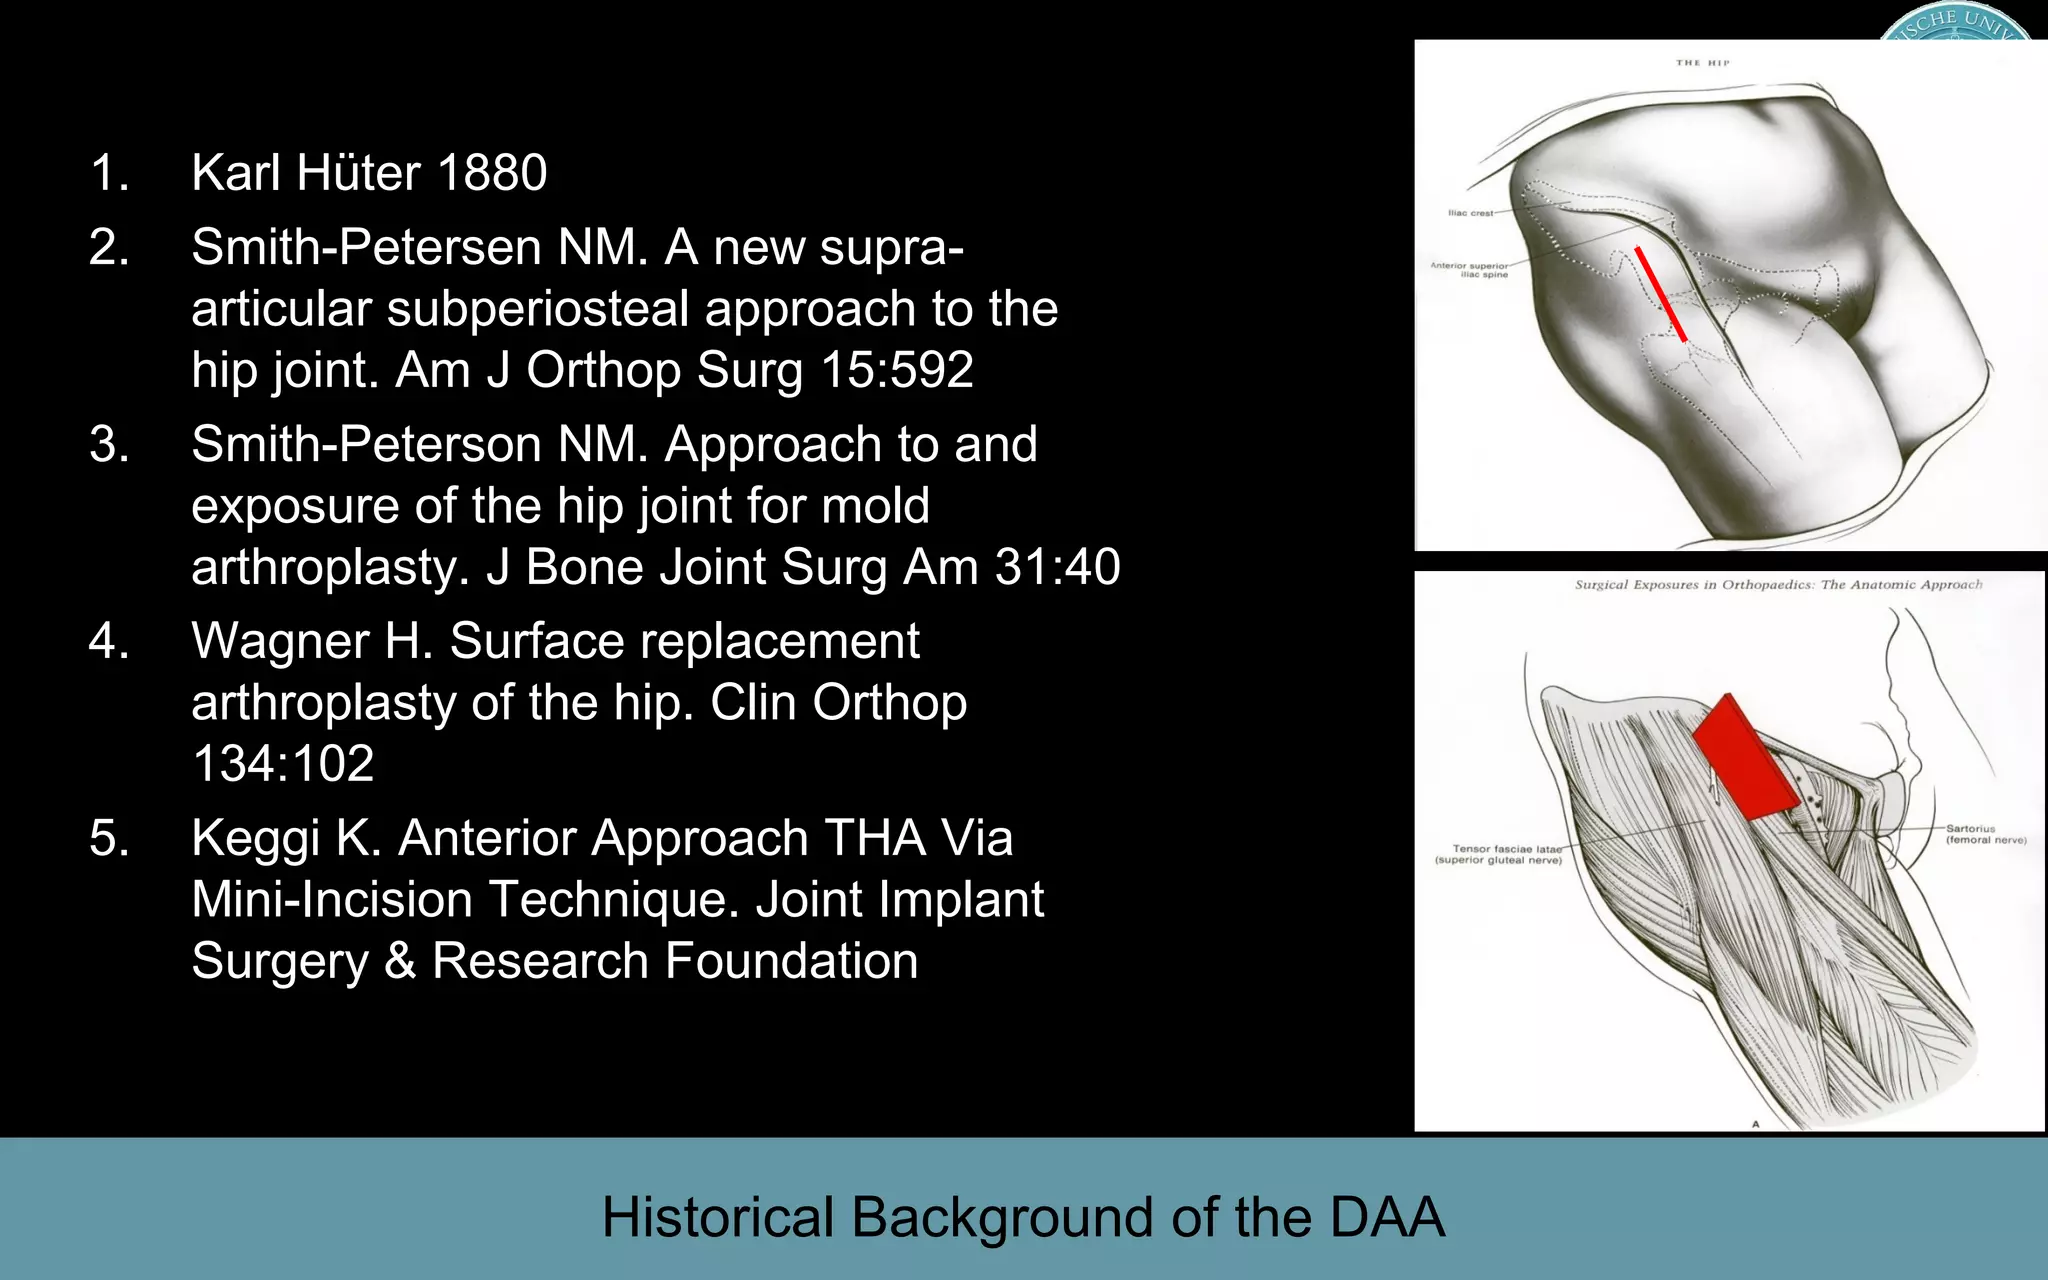

This document discusses the direct anterior approach for total hip arthroplasty. It lists advantages of the direct anterior approach such as increased stability, easier leg length equalization, lower costs by not requiring an operating table, reduced radiation exposure, faster rehabilitation, and lower risk of deep vein thrombosis. The document also discusses the historical background of the direct anterior approach, showing it has been performed since the 1880s. It presents images showing fatty degeneration of muscles and gluteal atrophy after total hip arthroplasty. Finally, it displays graphs comparing outcomes and improvements in quality of life domains between the direct anterior approach and minimally invasive approaches.